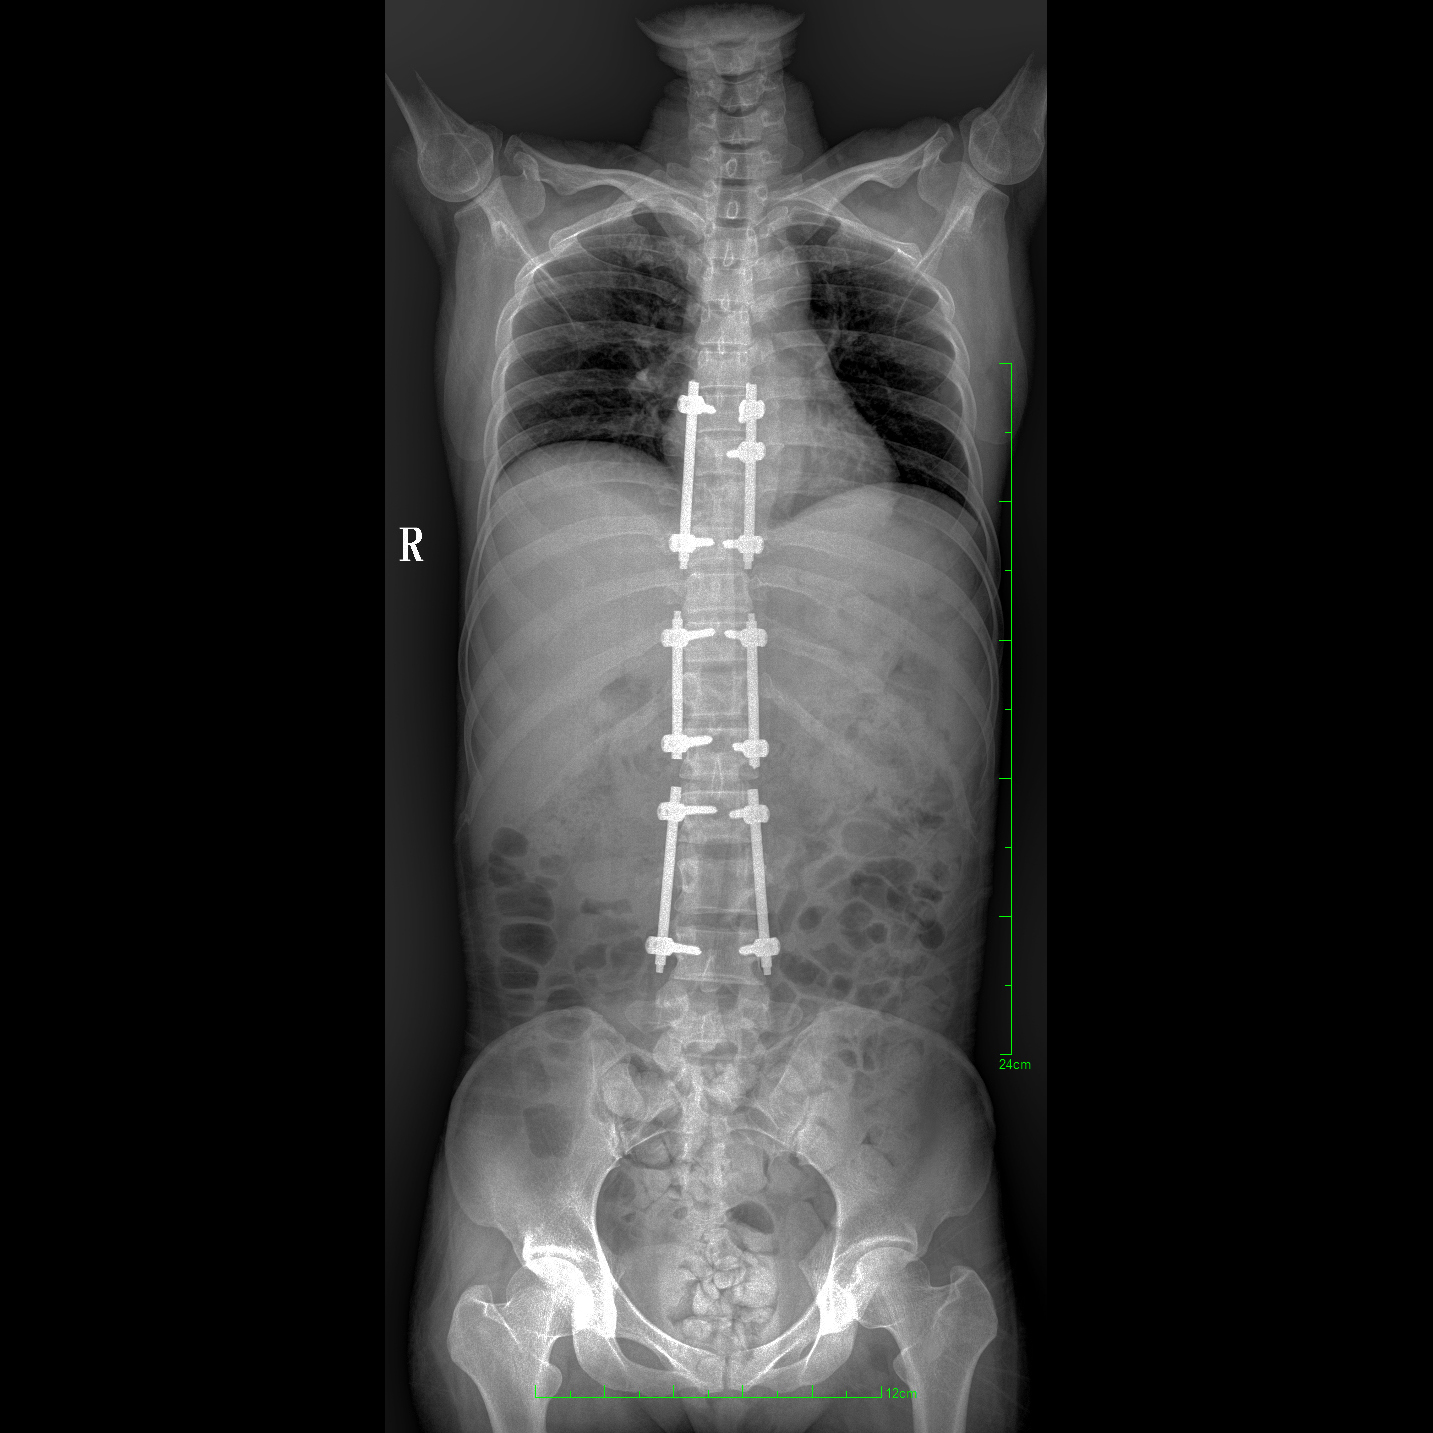

17"*34"有效視野,一次成像不拼接。相較于多張攝影再軟件拼接的DR設(shè)備,PLX8600解決了拼接圖像存在密度不均勻,拼接處圖像配準(zhǔn)和放大效應(yīng)等問(wèn)題,給臨床帶來(lái)了大視野影像解決方案,可一次性覆蓋全脊柱或雙下肢影像。

支持全脊柱攝影、雙下肢攝影、脊髓造影、復(fù)雜創(chuàng)傷、人工關(guān)節(jié)置換、關(guān)節(jié)損傷的修復(fù)重建等大視野臨床應(yīng)用

除常規(guī)靜態(tài)攝影外,PLX8600大平板具備動(dòng)態(tài)透視和點(diǎn)片功能,透視采集功能可支持大視野、多角度的可視化觀察。通過(guò)可視化的動(dòng)態(tài)影像,配合點(diǎn)片功能,能夠很好的觀察復(fù)雜部位病灶,有效的抓取關(guān)鍵幀,降低患者多次攝片的概率。如:全脊柱狀態(tài)評(píng)估、長(zhǎng)骨關(guān)節(jié)活動(dòng)度、下肢靜脈造影瓣膜功能評(píng)估、消化道功能評(píng)估、脊髓造影等更多大視野臨床應(yīng)用。